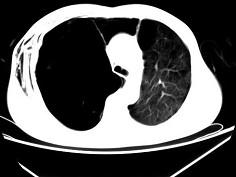

问题 男,32岁,被车撞伤后1小时,请结合影像图像选择其最可能的诊断为 ( )

选项 A、右侧肺大疱并皮下纵隔气肿 B、支气管断裂 C、右肺不张 D、右侧气胸并皮下纵隔气肿 E、右侧气胸

答案 D